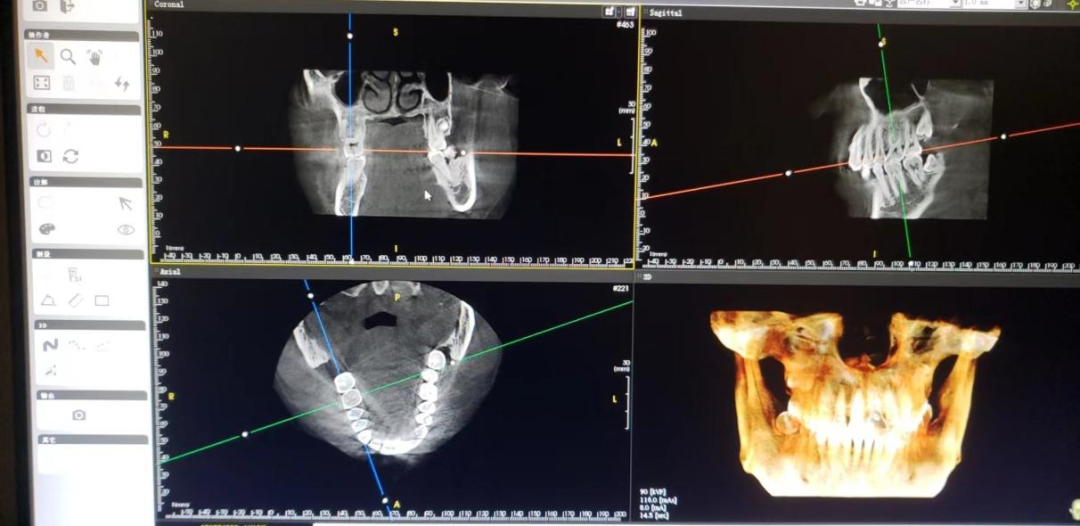

术前术后影像对比

术前CBCT显示:右上六冠根折裂至髓室底

术后CBCT显示:植体植入完成后

注:以上病例为术后即刻影像,

后续跟进更新复诊成骨影像